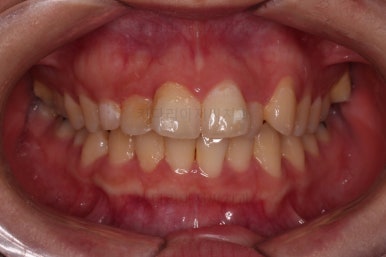

1. 초진

초진 시 입안의 모습입니다.

앞니쪽이 조금 삐뚤어 보인다는 점 이외에는 큰 문제점이 보이지 않죠?

어금니쪽을 자세히 관찰해 보면, 위아래 어금니의 맞물림(교합)이 어긋나 있는데요.

톱니바퀴처럼 물려야 되는 교합이 한 칸 씩 윗니가 아랫니보다 앞으로 나가있는 앵글씨 2급 부정교합 상태였습니다.